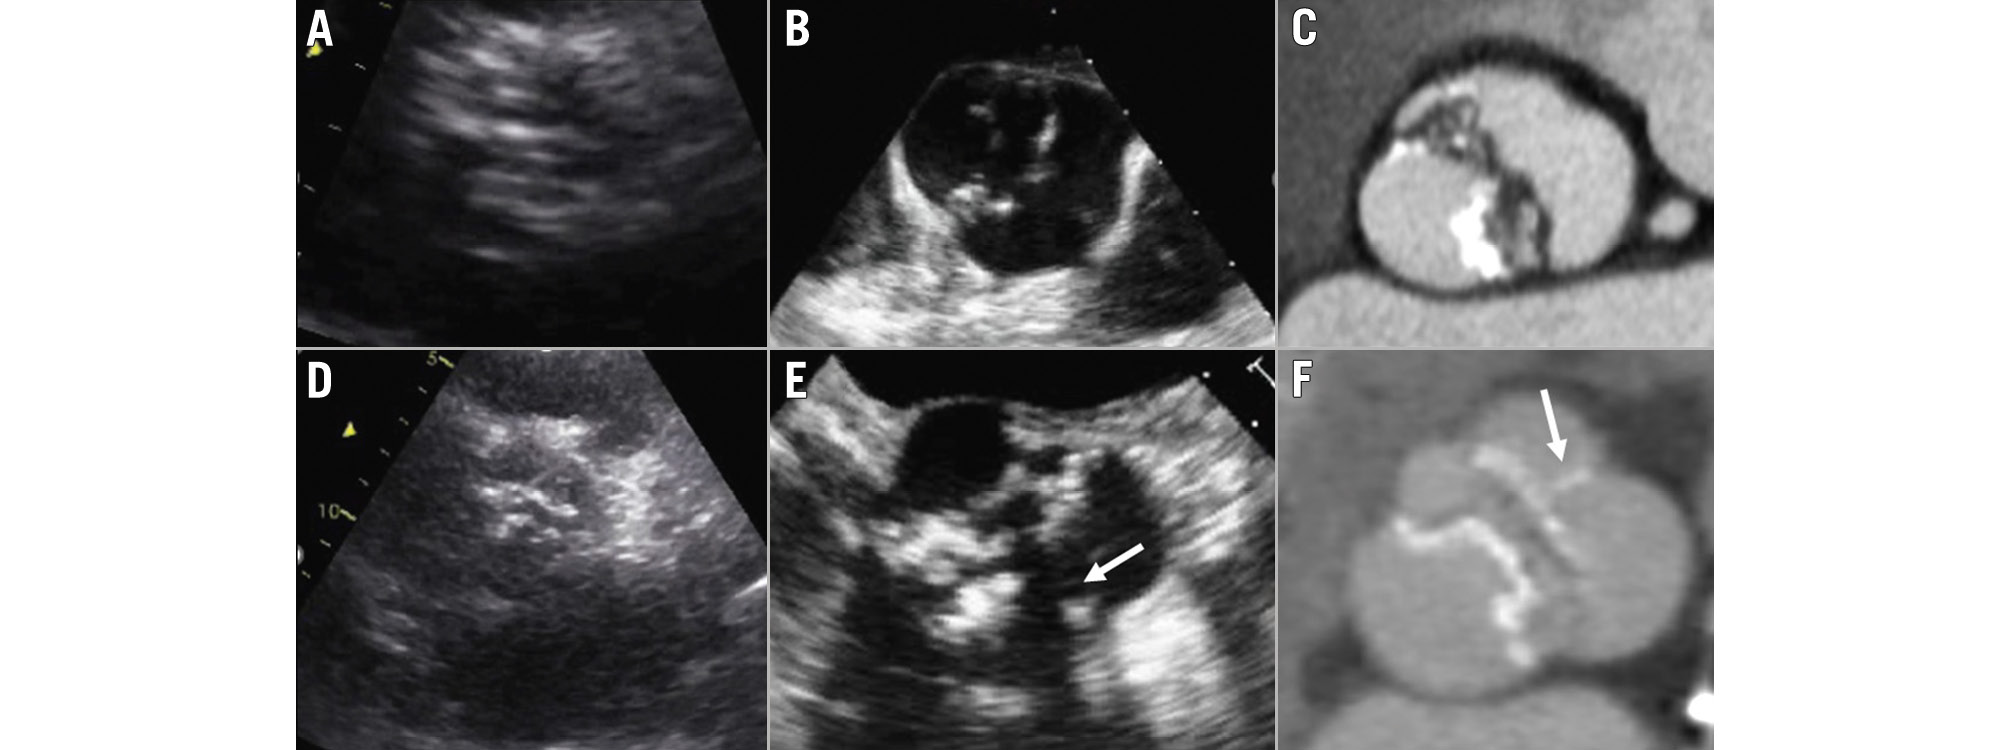

Assessment of the aortic valve anatomy (tricuspid vs bicuspid) is carried out from the parasternal short-axis view. A tricuspid valve has 3 commissures and 3 cusps, whereas a bicuspid valve has 2 commissures and 2 cusps, or 3 commissures and 2 functional cusps due to the presence of a fusion raphe between 2 of the 3 cusps (Figure 2). When the acoustic window is not appropriate, a transoesophageal echocardiography provides a more accurate assessment of the aortic valve anatomy. If the aortic valve is calcified, differentiation between a bicuspid and a tricuspid valve anatomy may be challenging. In those cases, CT provides the highest spatial resolution to assess the anatomy of the aortic valve (Figure 2). Cine images of the short axis of the aortic valve acquired with cardiac magnetic resonance imaging (CMR) can also provide an accurate evaluation of the aortic valve anatomy. In order to avoid artefacts when using 3D-imaging techniques, data acquisition should be performed with electrocardiogram (ECG)-gating. This is particularly important when assessing the dimensions of the aortic root and ascending aorta. When using transthoracic echocardiography, the aortic root and ascending aorta are visualised in the parasternal long-axis view, and dimensions are measured using the leading-to-leading edge method in diastole (Figure 3).

Figure 2. Anatomy of the aortic valve. Images (A), (B) and (C) show the transthoracic and transoesophageal echocardiograms and computed tomography of a patient with a bicuspid aortic valve with 2 commissures and 2 cusps. Images (D), (E) and (F) show the transthoracic and transoesophageal echocardiograms and computed tomography of a patient with a bicuspid aortic valve with 2 commissures and 3 cusps, 2 of which are fused by a fusion raphe (arrow).